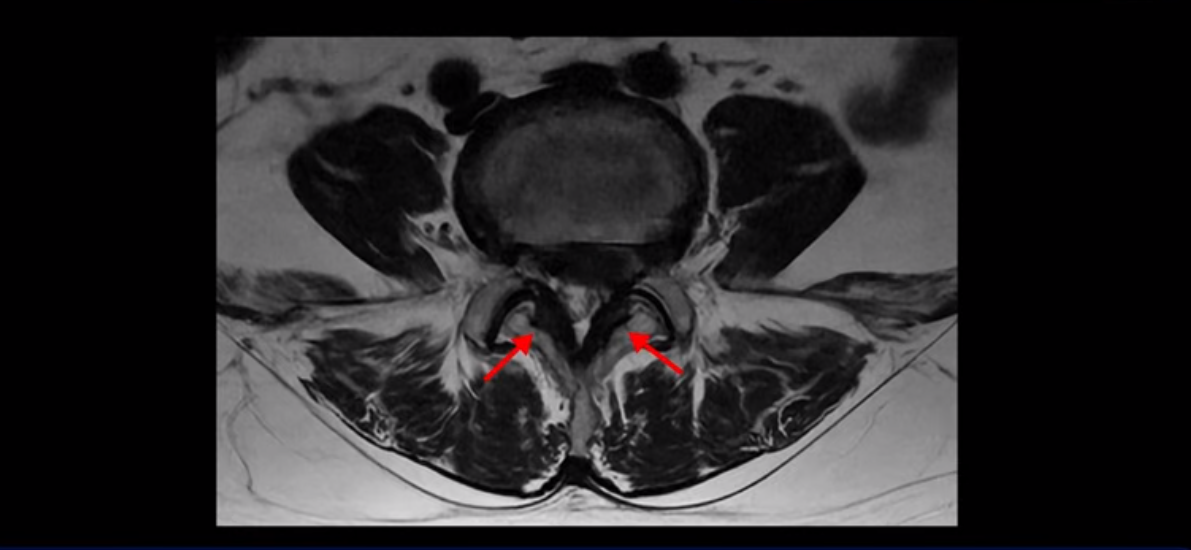

좌우 뒤쪽에는 황색 인대가 두꺼워져 있습니다.

앞에서는 디스크 수핵이 신경 공간으로 침범하고 뒤에서는 두꺼워진 인대가 신경 공간을 좁히고 있습니다.

이렇게 신경 공간이 좁아진 것을 협착이라고 합니다. 왼쪽으로 신경 구멍이 더 좁아져 있으니까 처음에는 왼쪽 엉덩이와 다리가 아팠는데 몇 년 동안 주사 맞으면서 버티다 보니까 오른쪽 다리까지 아프게 됩니다. 결국 양쪽 다리가 너무 아파서 5분 걷기도 힘들어지게 됩니다.

디스크 파열은 심해 보이나 신경 구멍이 좁아지는 협착증으로 보자면 저희 다른 치료 후기에 나오시는 협착증 환자분들의 MRI에 비해 신경 구멍은 넓은 편입니다. 그래서 신경이 정말 심하게 눌릴 때 나타나는 다리의 힘 빠짐 증상은 없었고 통증, 즉 아프다는 증상을 제일 심하게 호소하셨습니다.